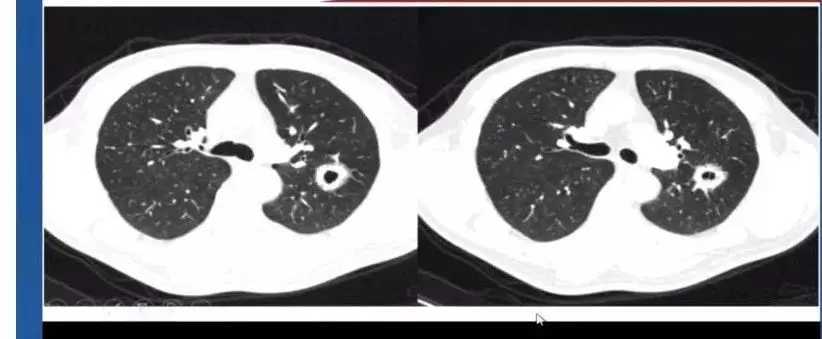

6. 肺结核

肺结核征象同样多变 ,常见为周围卫星灶及磨玻璃样改变,易被误诊为其他感染性疾病,需要实验室检查支持如T-SPOT等进行诊断。

结核空洞通常周围为薄壁空洞、壁均匀、细支气管受累、肺野内出现树芽征。

图9 左下肺结核空洞表现